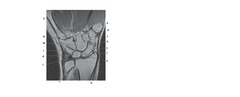

arthr/o

Front

joint

Back